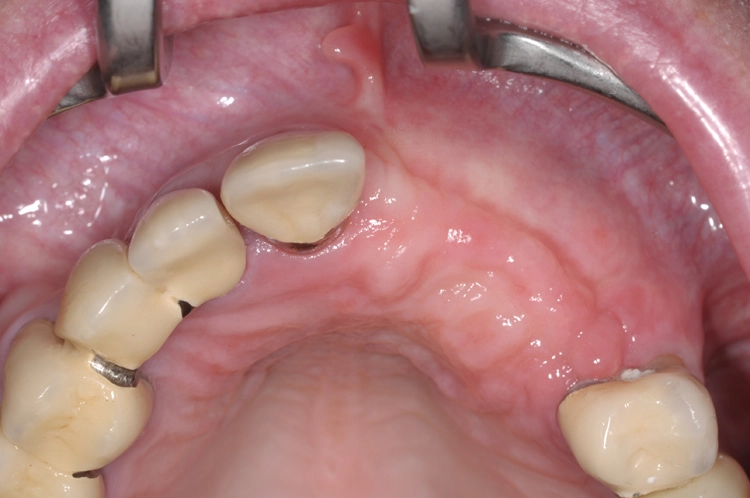

Ein 64 Jahre alter männlicher Patient ohne anamnestische Auffälligkeiten wurde mit dem Wunsch nach einer festsitzenden und ästhetisch ansprechenden Lösung im Frontzahnbereich von seinem Hauszahnarzt zur weiteren implantologischen Rehabilitation an unsere Praxis überwiesen. Nach eingehender klinischer Untersuchung wurde anhand einer 3D-Röntgenaufnahme mittels DVT das knöcherne Lager in der zu behandelnden Region beurteilt, worauf sich ein ausgeprägtes horizontales Knochendefizit zeigte, das eine Implantation in korrekter prothetischer Lage nicht zuließ (Abb. 1-3).

Die Entscheidung fiel daraufhin auf ein zweizeitiges Vorgehen mit vorheriger Knochenaugmentation in Schalentechnik und späterer Implantation von zwei BLT-Implantaten mit augmentativem Relining: Der Patient entschied sich nach ausführlicher Beratung und Vorstellung der alternativen Augmentationsmöglichkeiten für die Schalentechnik mit allogenen Kortikalisplatten und Granulaten (maxgraft® spongiosa, Straumann), wie die Abbildungen 4 bis 7 dokumentieren.

Nach einer viermonatigen Einheilphase erfolgte die Implantation von zwei Straumann® BLT Implantaten mit einer Länge von 12 mm und einem Durchmesser von 4,1 mm im Bereich des aufgebauten Knochens (Ausgangssituation siehe Abb. 8). Vor der Implantation fand vorbereitend eine Glättung der Oberfl äche statt, um scharfe Kanten zu beseitigen (Abb. 9). Für die korrekte prothetische Positionierung der Implantate kamen individuell gefertigte Orientierungsschablonen zum Einsatz, anschließend wurden die Implantate für eine verschraubte Brücke gesetzt (Abb. 10).